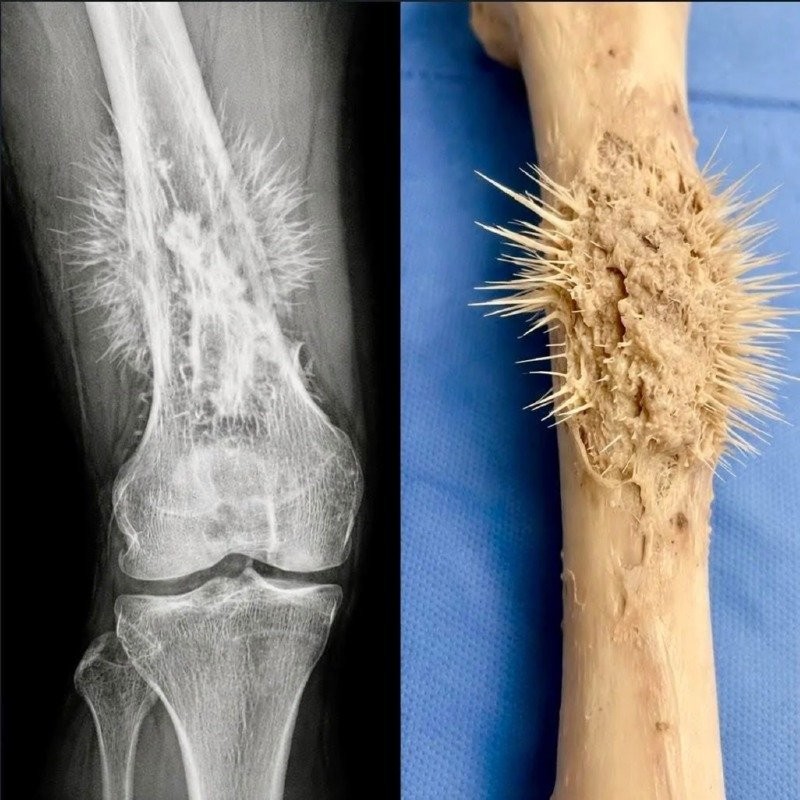

약혐)뼈에 암이 생기는 병, 골육종